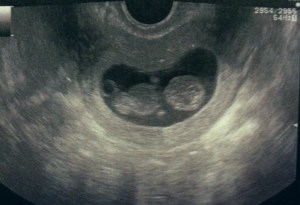

Lunedì ho fatto l’ennesima eco, ormai ho perso il conto. La ginecologa mi compatisce, ma penso che si prenda i miei soldi volentieri, e visto che io sono ben felice di investire lo stipendio per calmare la mia ansia, posso dire che siamo tutti soddisfatti.

Sesamino sta bene, cresce alla velocità della luce, le sue dimensioni (quasi 4 cm, ma ormai sarà diventato ancora più grande), sono perfettamente in linea con la settimana in cui mi trovo.

Ogni volta che lo vedo mi meraviglio nel constatare quanto sia cresciuto… Lui è qui, nel mio grembo, si nutre, si sviluppa, vive, cresce! E’ un miracolo, è un bellissimo miracolo.

Lunedì ci ha fatto una bella sorpresa… Mentre la ginecologa faceva l’eco, Sesamino ha iniziato a muoversi… Muoveva le braccia e le gambe come un indemoniato! E’ stato un momento meraviglioso… Era la prima volta che lo vedevamo muoversi! (Secondo me l’abbiamo svegliato e quello era il suo modo per lamentarsi ih ih).